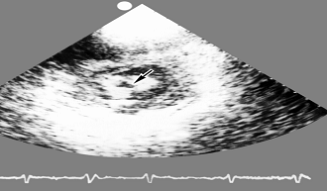

Рис. 23б). Одномерная эхокардиограмма больного с тромбом в левом желудочке сердца: на двухмерной эхокардиограмме в полости левого желудочка (темное поле) определяется интимно связанное со стенкой и выбухающее в полость плотное эхопозитивное образование (указано стрелкой), которое в одномерном изображении представляется слоистым, заполняющим почти всю полость левого желудочка

Рис. 23а). Двухмерная эхокардиограмма больного с тромбом в левом желудочке сердца: на двухмерной эхокардиограмме в полости левого желудочка (темное поле) определяется интимно связанное со стенкой и выбухающее в полость плотное эхопозитивное образование (указано стрелкой), которое в одномерном изображении представляется слоистым, заполняющим почти всю полость левого желудочка